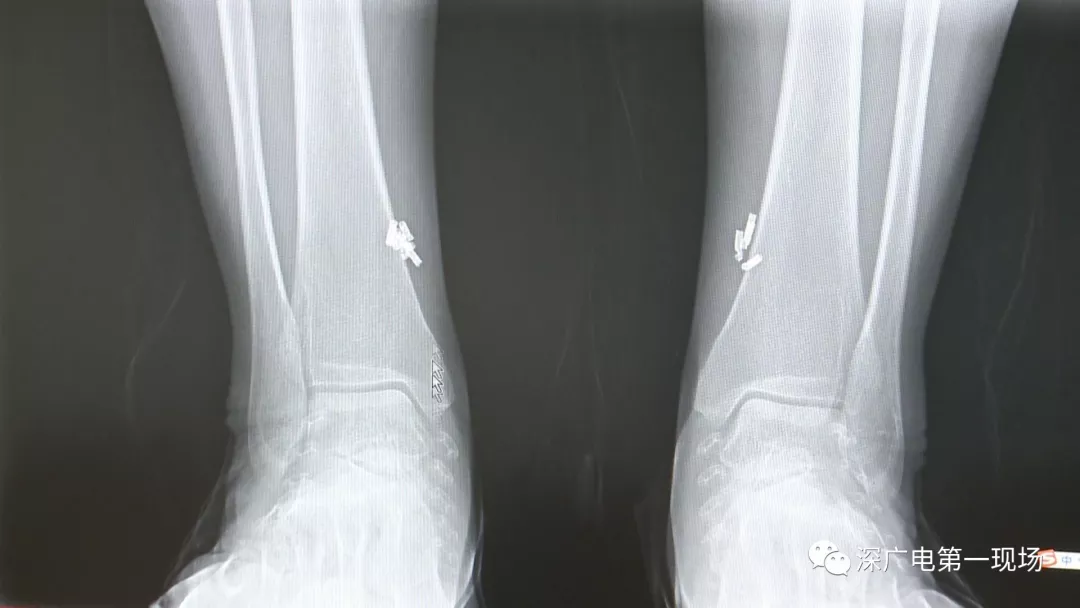

從X光影像圖片中可以看到

患者周身布滿了彈簧圈

深圳大學(xué)總醫(yī)院神經(jīng)外科副主任醫(yī)師陳富勇介紹,當(dāng)時(shí)檢查的時(shí)候發(fā)現(xiàn),該患者從頭部到腿部,基本上每個(gè)地方都有彈簧,很難數(shù)清具體數(shù)目。